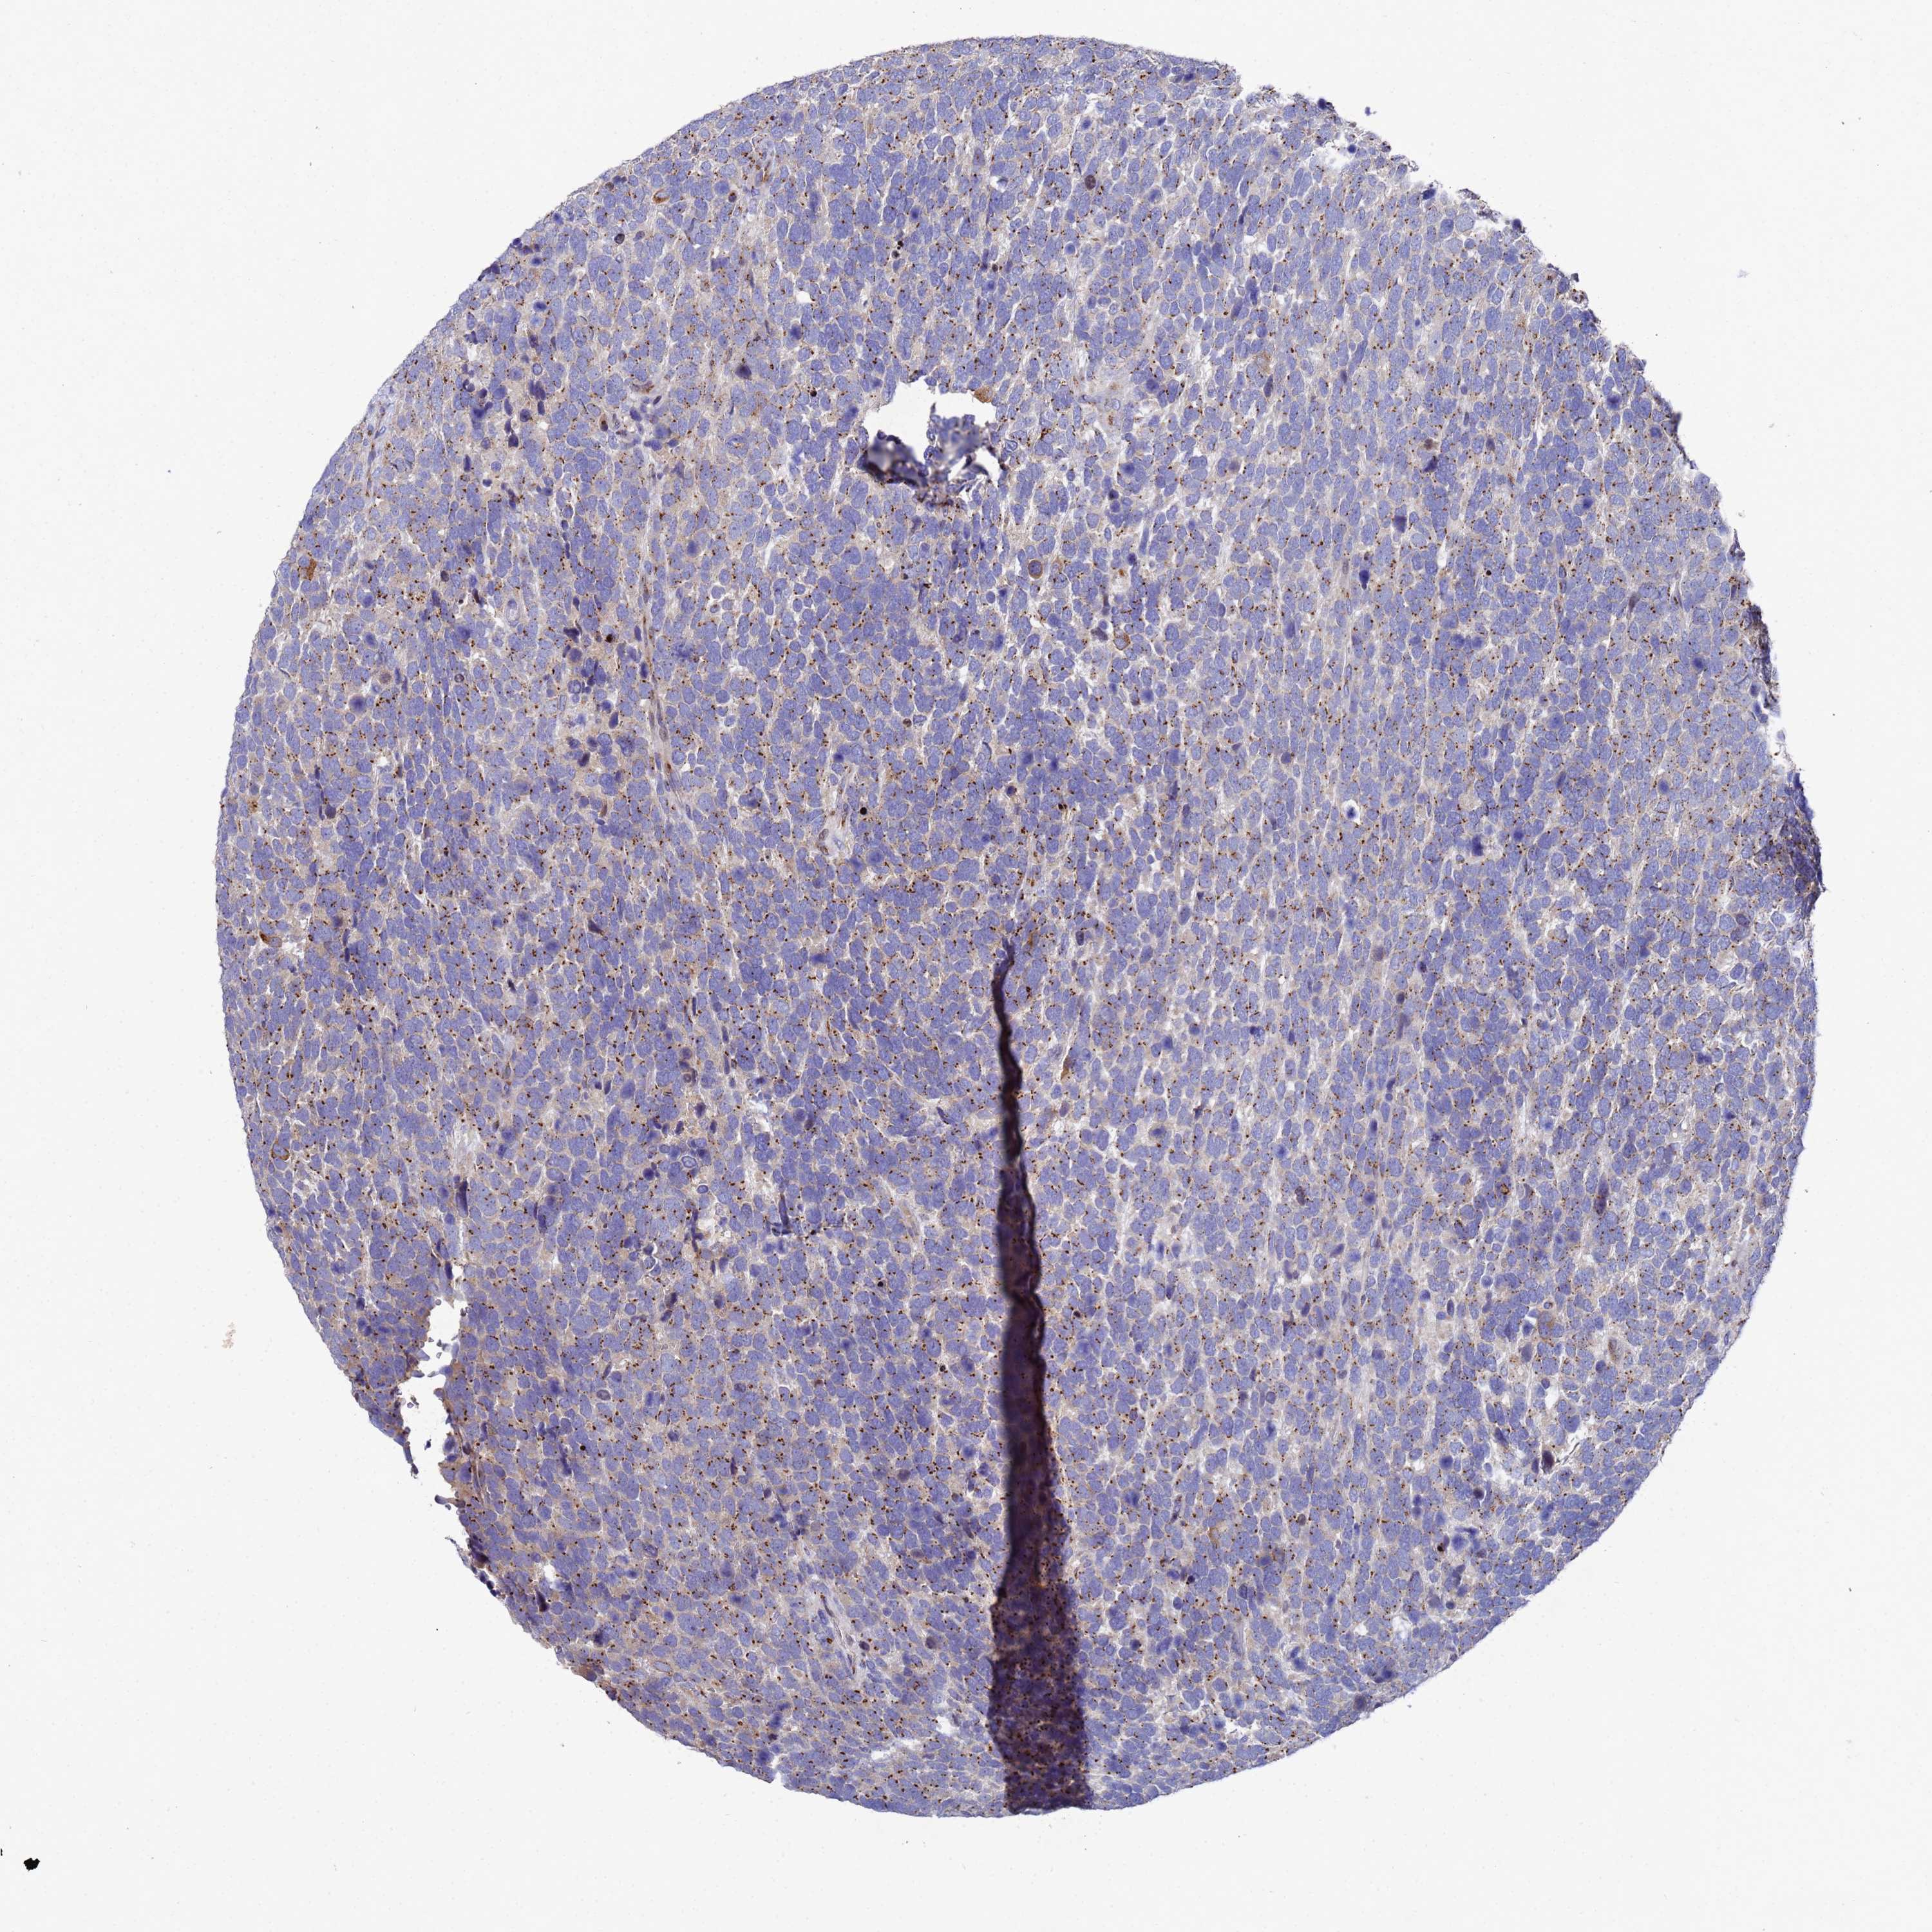

UROTHELIAL CANCER - Protein expressioni

A mouse-over function shows sample information and annotation data. Click on an image to view it in a full screen mode. Samples can be filtered based on level of antibody staining by selecting one or several of the following categories: high, medium, low and not detected. The assay and annotation is described here.

Note that samples used for immunohistochemistry by the Human Protein Atlas do not correspond to samples in the TCGA dataset.

Antibody stainingi

Antibody staining in the annotated cell types in the current human tissue is reported as not detected, low, medium, or high, based on conventional immunohistochemistry profiling in selected tissues. This score is based on the combination of the staining intensity and fraction of stained cells.

Each image is clickable and will lead to virtual microscopy that enables deeper exploration of all samples and also displays staining intensity scores, fraction scores and subcellular localization as well as patient and tissue information for each sample.

Antibody HPA045902

Staining

High

Medium

Low

Not detected

Intensity

Strong

Moderate

Weak

Negative

Quantity

>75%

75%-25%

<25%

None

Location

Nuclear

Cytoplasmic/membranous

Cytoplasmic/membranous,nuclear

Urothelial carcinoma, High grade